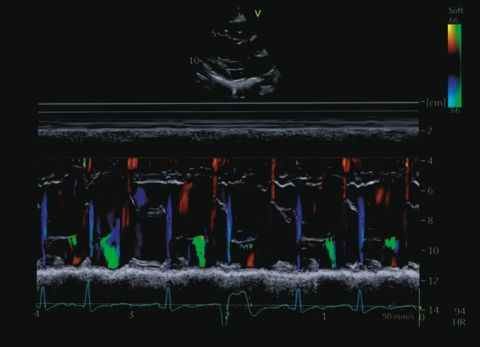

Wideo Echokardiografia. Przypadek 16

prof. dr hab. n. med. Olga TrojnarskaCiężarna pacjentka ze szmerem skurczowym.